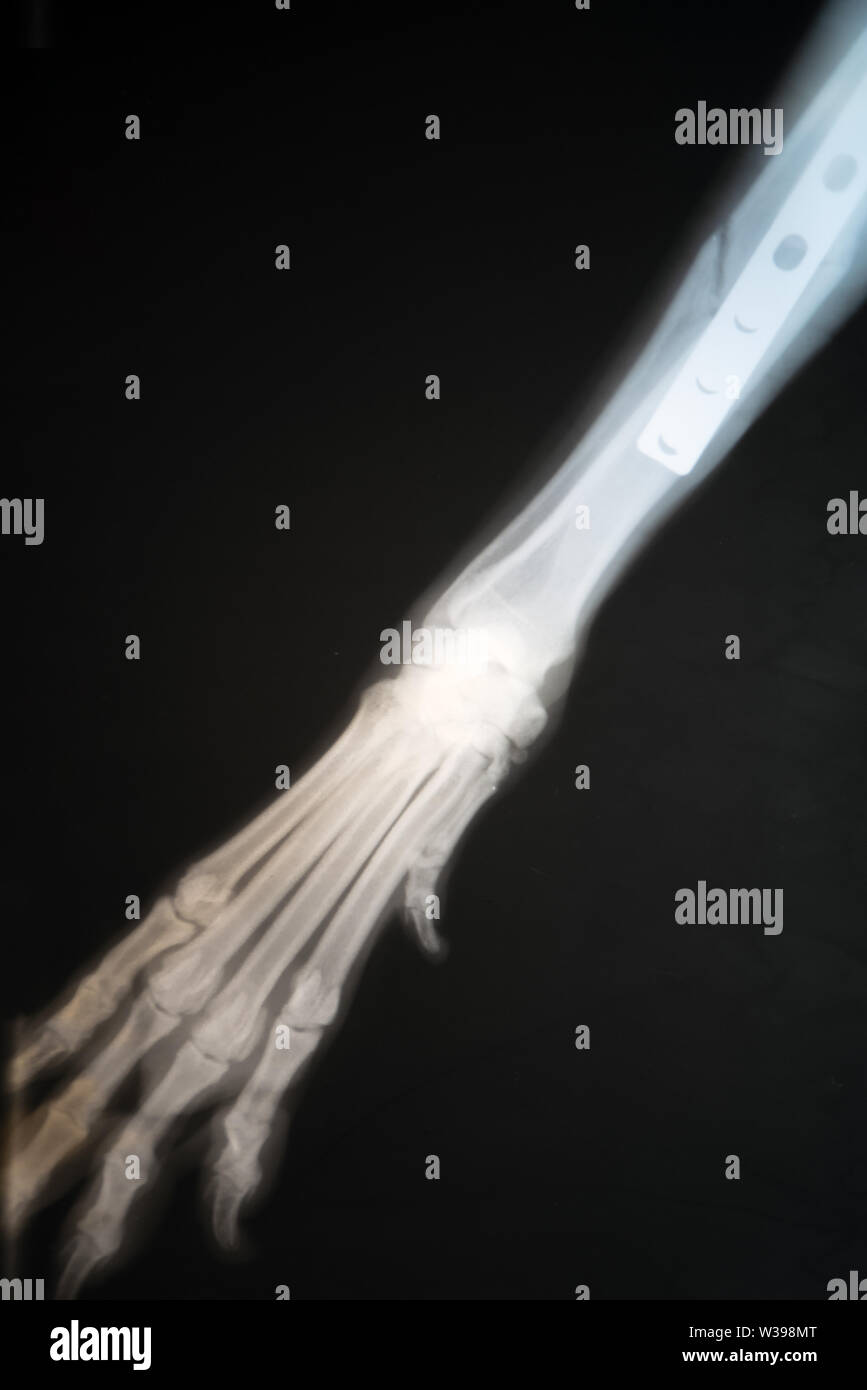

Xray del cane frattura della zampa. La radiografia la zampa rotta di un cane Foto stock Alamy Cane Rotto La Zampa Riconoscere questa lesione è fondamentale per garantirgli un trattamento. Hai mai sospettato che il tuo cane possa essersi rotto una zampa? Scopriamo insieme come riconoscere i sintomi di una zampa rotta o slogata e come fornire le prime cure per aiutare il tuo cane a sentirsi meglio. Scopri come capire se il cane si è rotto la zampa: Se abbiamo. Cane Rotto La Zampa.